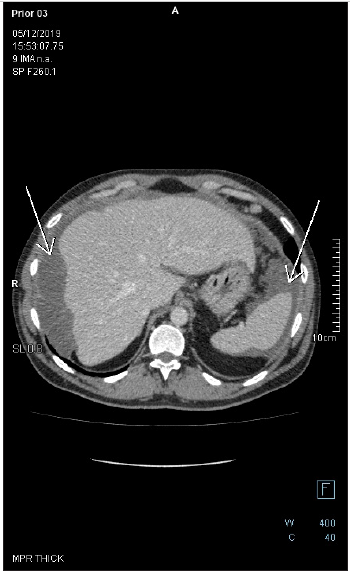

Figure 5: Axial-CECT of the upper abdomen reveals perihepatic and perisplenic mucinous deposits. There is a faint soft tissue circumferential component in the perihepatic lesion, the wall of which is enhancing with no appreciable septation nor calcification. There is no fat stranding in the adjacent fat tissue.

Figure 6: Follow up axial-CECT of the upper abdomen reveals perihepatic and perisplenic mucinous deposits. There is a faint soft tissue component in the perihepatic lesion, the wall of which is enhancing with no appreciable septation nor calcification. There is no fat stranding in the adjacent fat tissue. Lesions are noticed to be stable on CECTs performed in years 2019 and 2020.